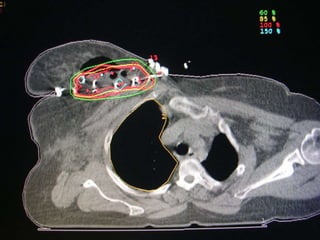

REGIONAL NODAL CONTOURING

SCF begins

Axillary level III begins

Axillary level II begins

Axillary level I begins

Axillary level I ends

IMC begins

IMC ends